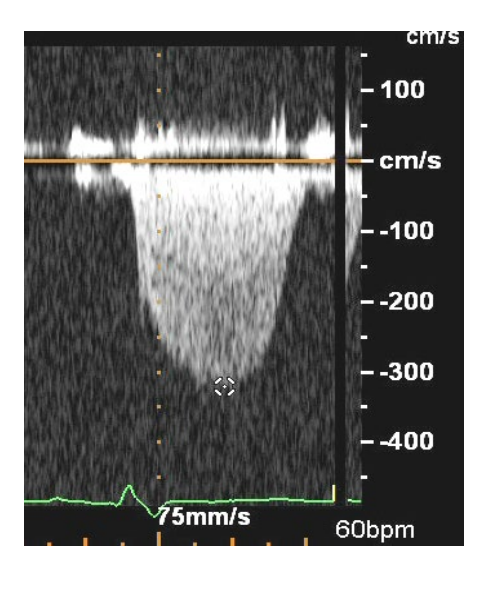

what does this image show?

PIG of Tricuspid Regurgitation

RVSP mmHg =

4( TR peak jet velocity 2) + RAP